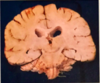

What plane is shown?

Horizontal section